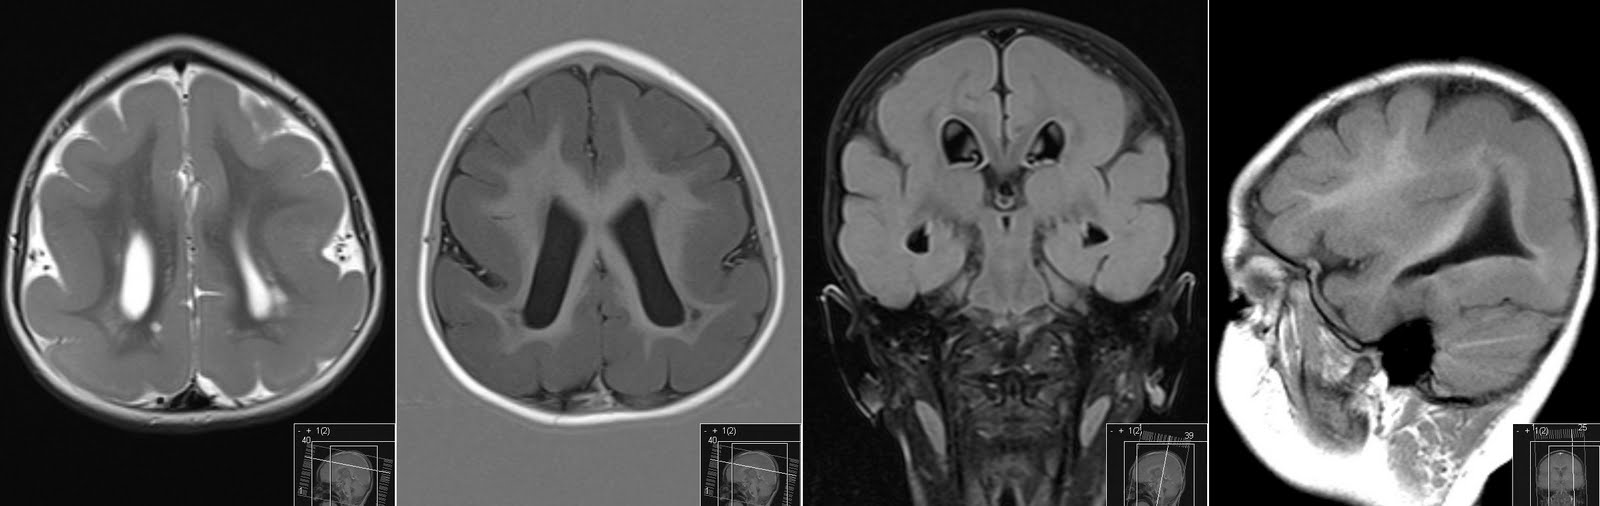

From radiologymri.blogspot.com

Cavum Velum Interpositum on MRI Cavum Velum Interpositum Effects Identify the etiology of cavum veli interpositi and the medical conditions. the term cyst of the velum interpositum or cavum veli interpositi cyst should be used when the lesion is of round. abstract cavum velum interpositi is the space between the layers of the tela choroidea of the third ventricle. cavum velum interpositi is the space between. Cavum Velum Interpositum Effects.

Radiology MRI Cavum Velum Interpositum on MRI Cavum Velum Interpositum Effects the term cyst of the velum interpositum or cavum veli interpositi cyst should be used when the lesion is of round. cavum veli interpositi is a rare anatomical variation characterized by an enlarged space within the velum. cavum velum interpositi is the space between the layers of the tela choroidea of the third ventricle. an enlarged. Cavum Velum Interpositum Effects.